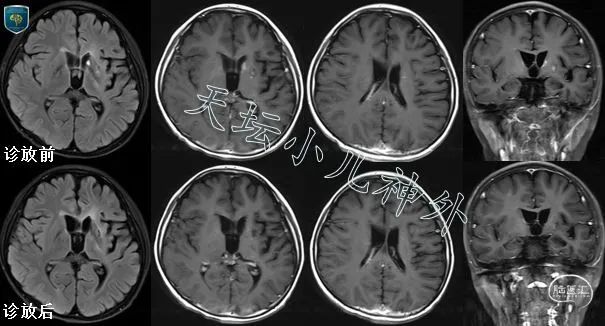

图2 典型基底节区生殖细胞瘤诊放病例。

10岁男性患儿,右侧肢体笨拙伴智力减退两年,进行性加重。头颅CT/MRI示:左侧底节区混杂信号影、散在不均匀强化;左侧颞叶萎缩;血清β-HCG(-)。本例高度怀疑左侧底节区生殖细胞瘤,行诊断性放疗,一月后复查,患儿诉右侧肢体笨拙缓解明显(自诉:浑身轻松);头颅CT/MRI示:左侧底节区病变范围明显缩小,强化灶消失。诊放效果明确,生殖细胞瘤诊断明确,顺利转入后续治疗。